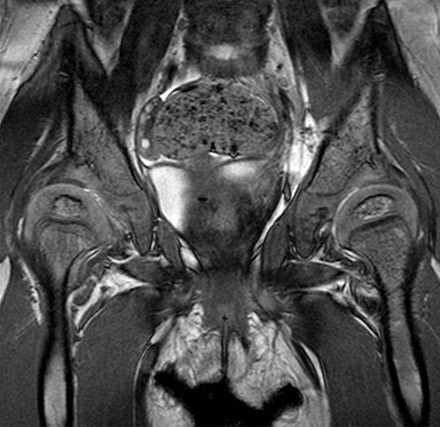

Een MRI-scan is een scan die wordt gemaakt met behulp van een magneetveld en radiogolven. MRI staat voor Magnetic Resonance Imaging. Met een MRI-scan is het mogelijk om de weke delen van een gewricht (alles behalve het bot) in beeld te brengen waardoor bij de heup bijvoorbeeld ook het labrum en het kraakbeen van het gewricht kunnen worden bekeken.

MRI van een kind van twee jaar. Dwarsdoorsnede door beide heupgewrichten: het kraakbeen van de heupkoppen is goed zichtbaar. Op een röntgenfoto is dit niet te zien.